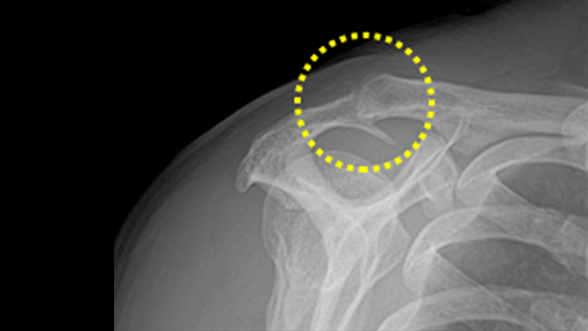

관절와순 파열(어깨관절 탈구)

관절와순은 어깨와 팔을 이어주며 어깨 관절의 움직임이 원활하도록 잡아주는 역할을 합니다.

관절와순이 어깨 뼈에서 이탈되어 손상을 입거나 찢어진 경우 관절와순 파열(어깨관절 탈구)이며,

증상이 심한 경우 인공관절 치환술을 시행하기도 합니다.

관절와순 파열(어깨관절 탈구)의 증상

비수술 치료 : 약물, 고정치료 (깁스 또는 보조기), 물리치료, 주사 치료, 도수 치료

수술치료 : 건봉성형술